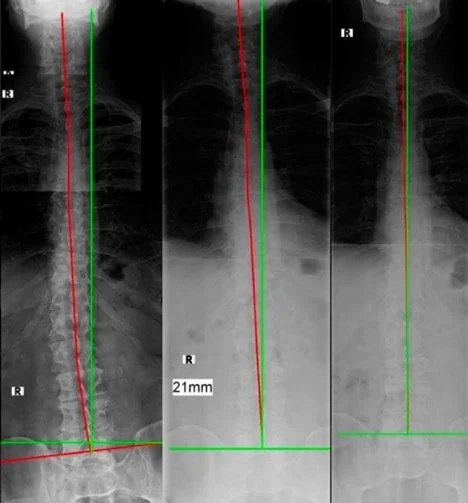

Various examples of structural abnormalities associated with left trunk list as seen on digital radiography (x-ray), green line represents normal alignment, red line represents patient's alignment.

Images demonstrating Structural Abnormalities in red with green line showing normal spinal reference position for more explanation please read from source:

E. Harrison, D. and P. A. Oakley (2022). An Introduction to Chiropractic BioPhysics® (CBP®) Technique: A Full Spine Rehabilitation Approach to Reducing Spine Deformities, IntechOpen.